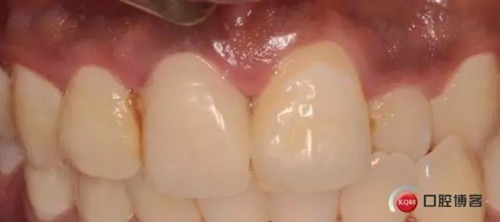

兩月后牙齦恢復(fù)正常穩(wěn)定。正式取模,E.max鑄瓷修復(fù)

可以看出牙齦袖口很漂亮,修復(fù)體外形也不錯,就是顏色偏白一點,讓患者改色,患者覺得已經(jīng)很滿意了,而且考慮其他牙以后做美白,所以不換了。

可以看出修復(fù)體的邊緣密合度都很好。希望這次修復(fù)能夠讓這顆牙多服役幾年吧